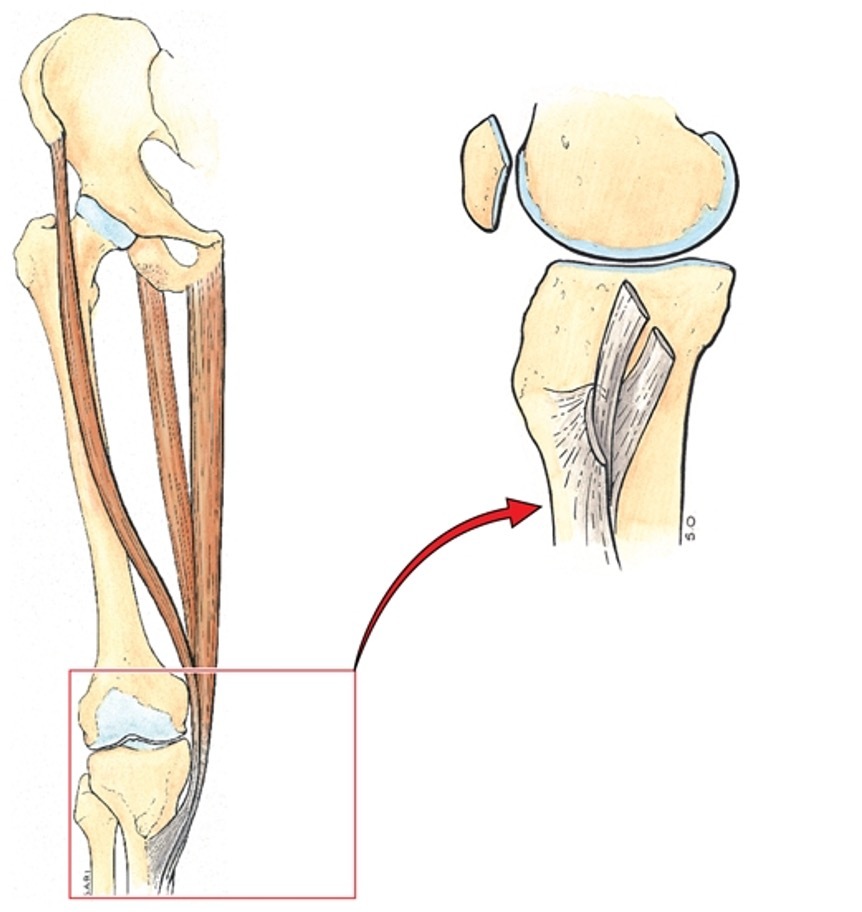

what are the 3 different muscles that insert at the medial aspect of the knee? [3]

which compartment are they all originally from? [3]

what is name for this meetin of three muscles? [3]

= pes anserinus !!